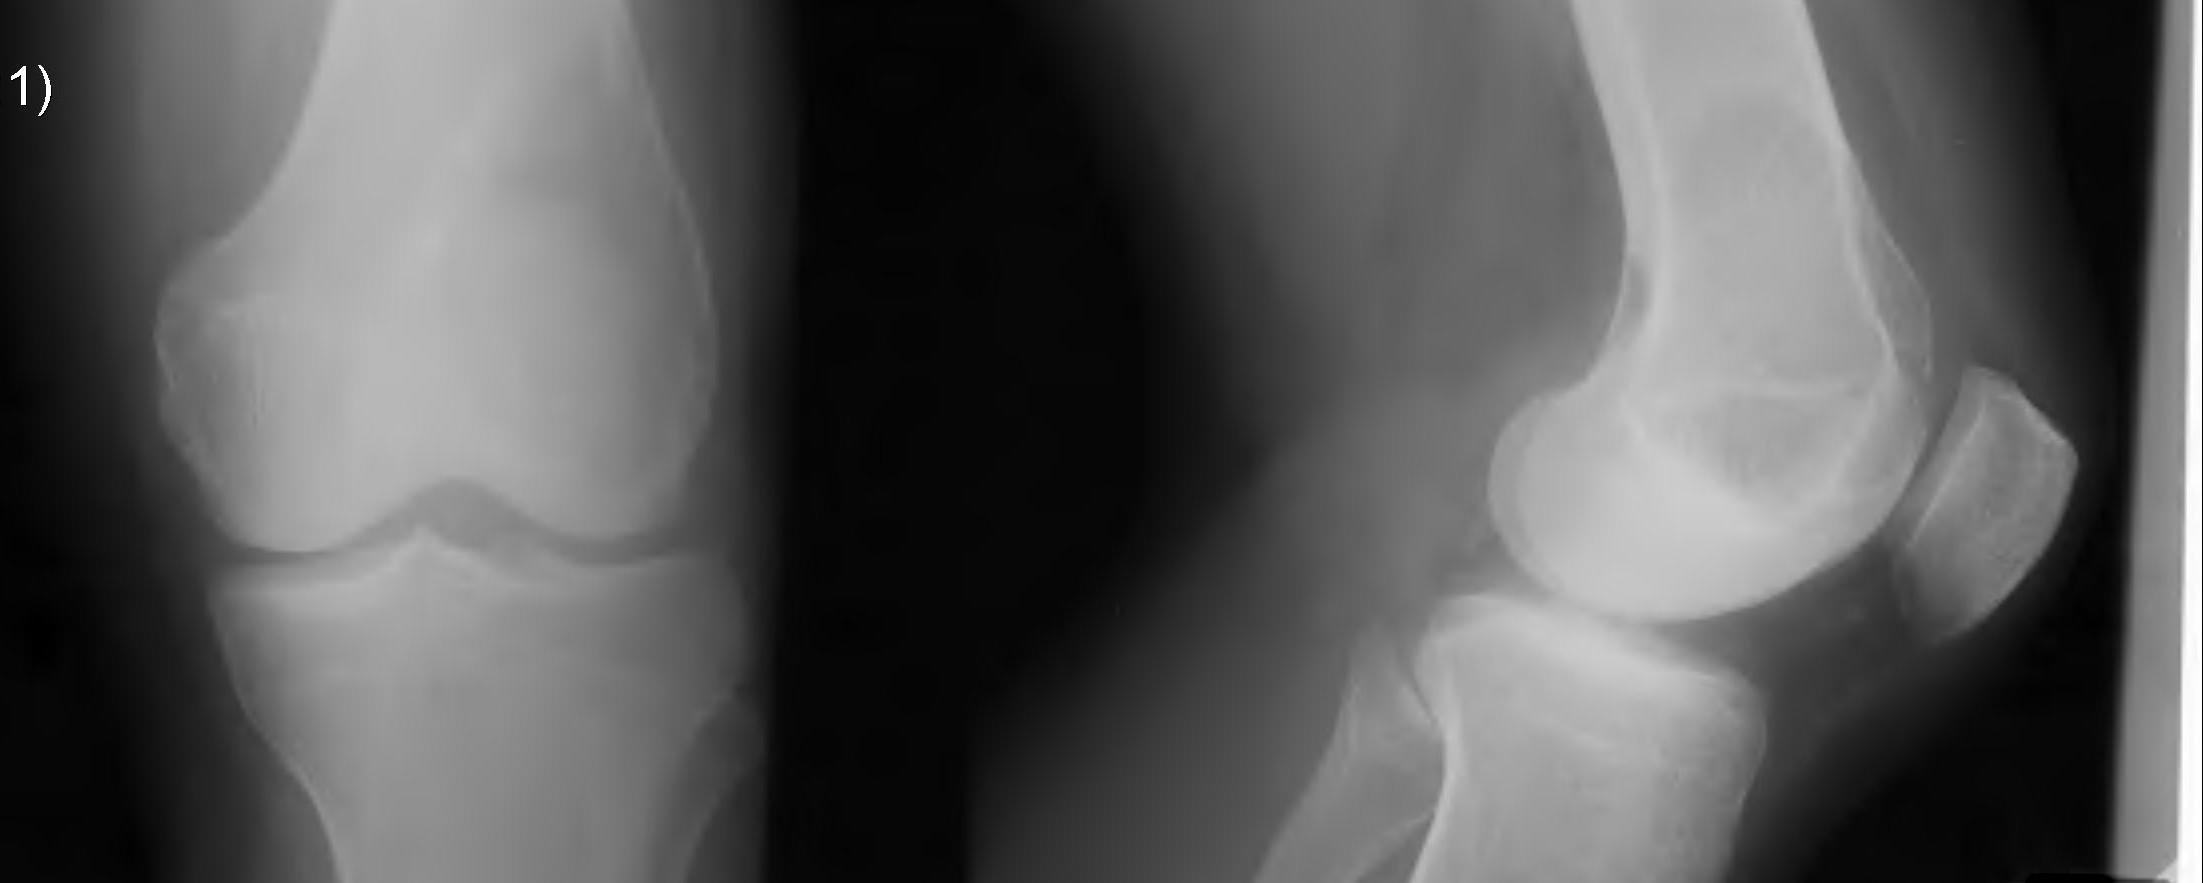

X-ray

Eccentric, sharply demarcated lytic lesion

- no sclerosis around lesion

- narrow zone of transition

- metaphysis, extending into epiphysis

- no mineralization

85% meta-epiphysis of long bones